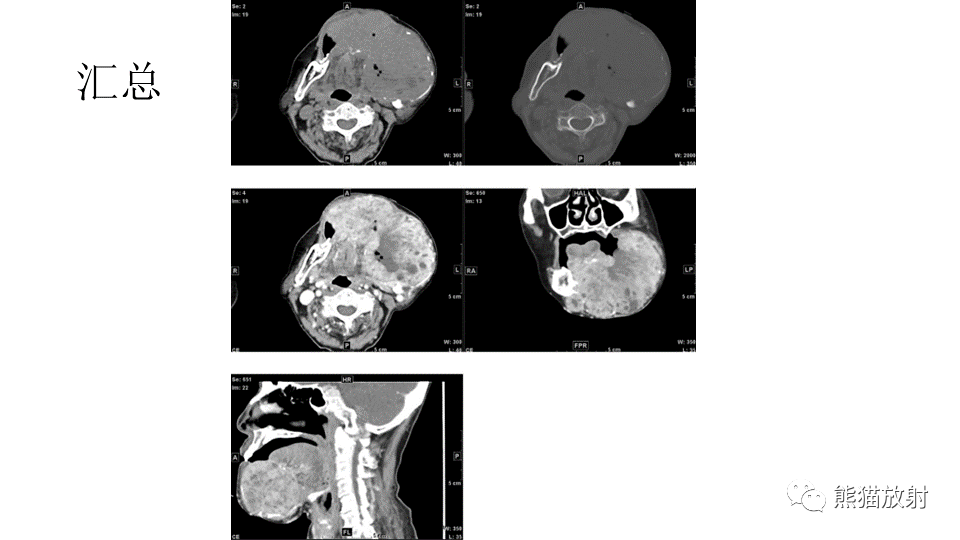

【病例】下颌骨成釉细胞瘤2例CT-7

【病例】下颌骨成釉细胞瘤2例CT-8

【病例】下颌骨成釉细胞瘤2例CT-9

【病例】下颌骨成釉细胞瘤2例CT-10